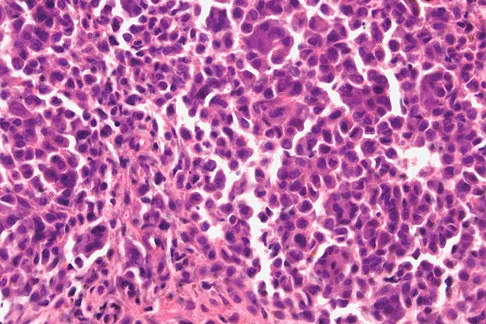

Figures 61a and 61b show the CT and MRI scans of a 40-year-old man who has hip pain. He undergoes total hip arthroplasty and curettage and cementation of the lesion as shown in Figure 61c. Histopathologic photomicrographs of the curettage specimen are shown in Figures 61d and 61e. What is the best course of treatment?

Explanation

The definitive surgery would be removal of the entire resection bed, and in this case of dedifferentiated chondrosarcoma, a hemipelvectomy was performed. The MRI and CT scans show an aggressive cartilage lesion. The histology, representative of a dedifferentiated chondrosarcoma, shows a bimorphic low-grade cartilage lesion with high-grade spindle cell sarcoma. The cartilage lesion is usually an enchondroma or low-grade chondrosarcoma. The dedifferentiated portion is typically a malignant fibrous histocytoma, osteosarcoma, or fibrosarcoma. Weber KL, Pring ME, Sim FH: Treatment and outcome of recurrent pelvic chondrosarcoma. Clin Orthop Relat Res 2002;397:19-28.